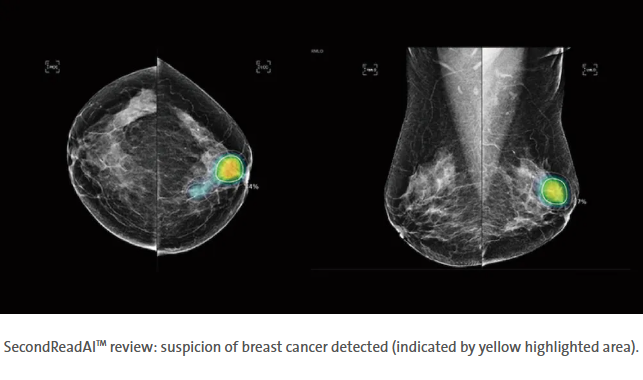

Did you know we use Artificial Intelligence to detect breast cancer?

Early detection of breast cancer is important for better outcomes and treatment options. That’s why our diagnostic radiologists use SecondRead AI™ after their initial review to support their professional analysis of your screening (non-symptomatic) mammogram. This AI technology provides an additional examination of your mammography images, pixel by pixel, to determine any suspicious areas that may be too small for human eyes to identify.